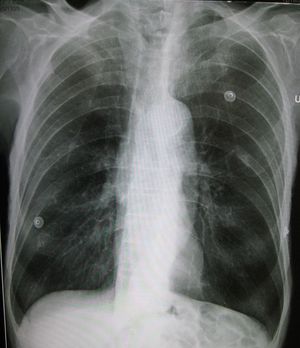

| صورة معبرة عن الموضوع نفاخ رئوي A lateral chest x-ray of a person with emphysema. Note the barrel chest and flat diaphragm. | |